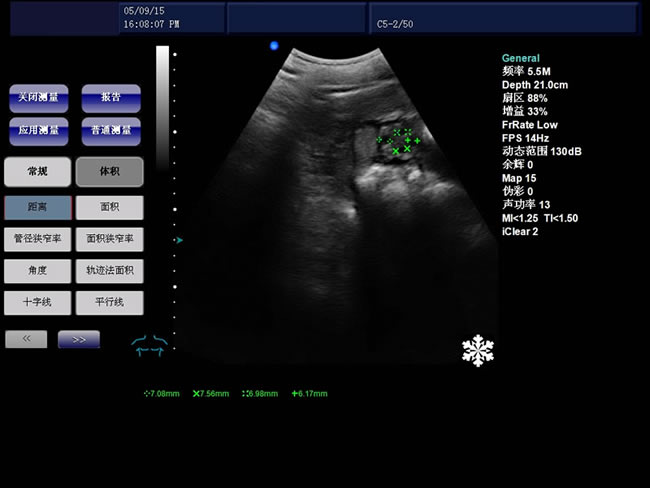

基本測量計(jì)算功能

B模式基本測量:距離、角度、周長和面積(橢圓法、軌跡法)、體積、直方圖、斷面圖

• S8彩色多普勒獸用超聲診斷儀是徐州市大為電子設(shè)備有限公司推出的一款全新的彩色超聲診斷儀器。

適用范圍:B超機(jī)產(chǎn)品性能